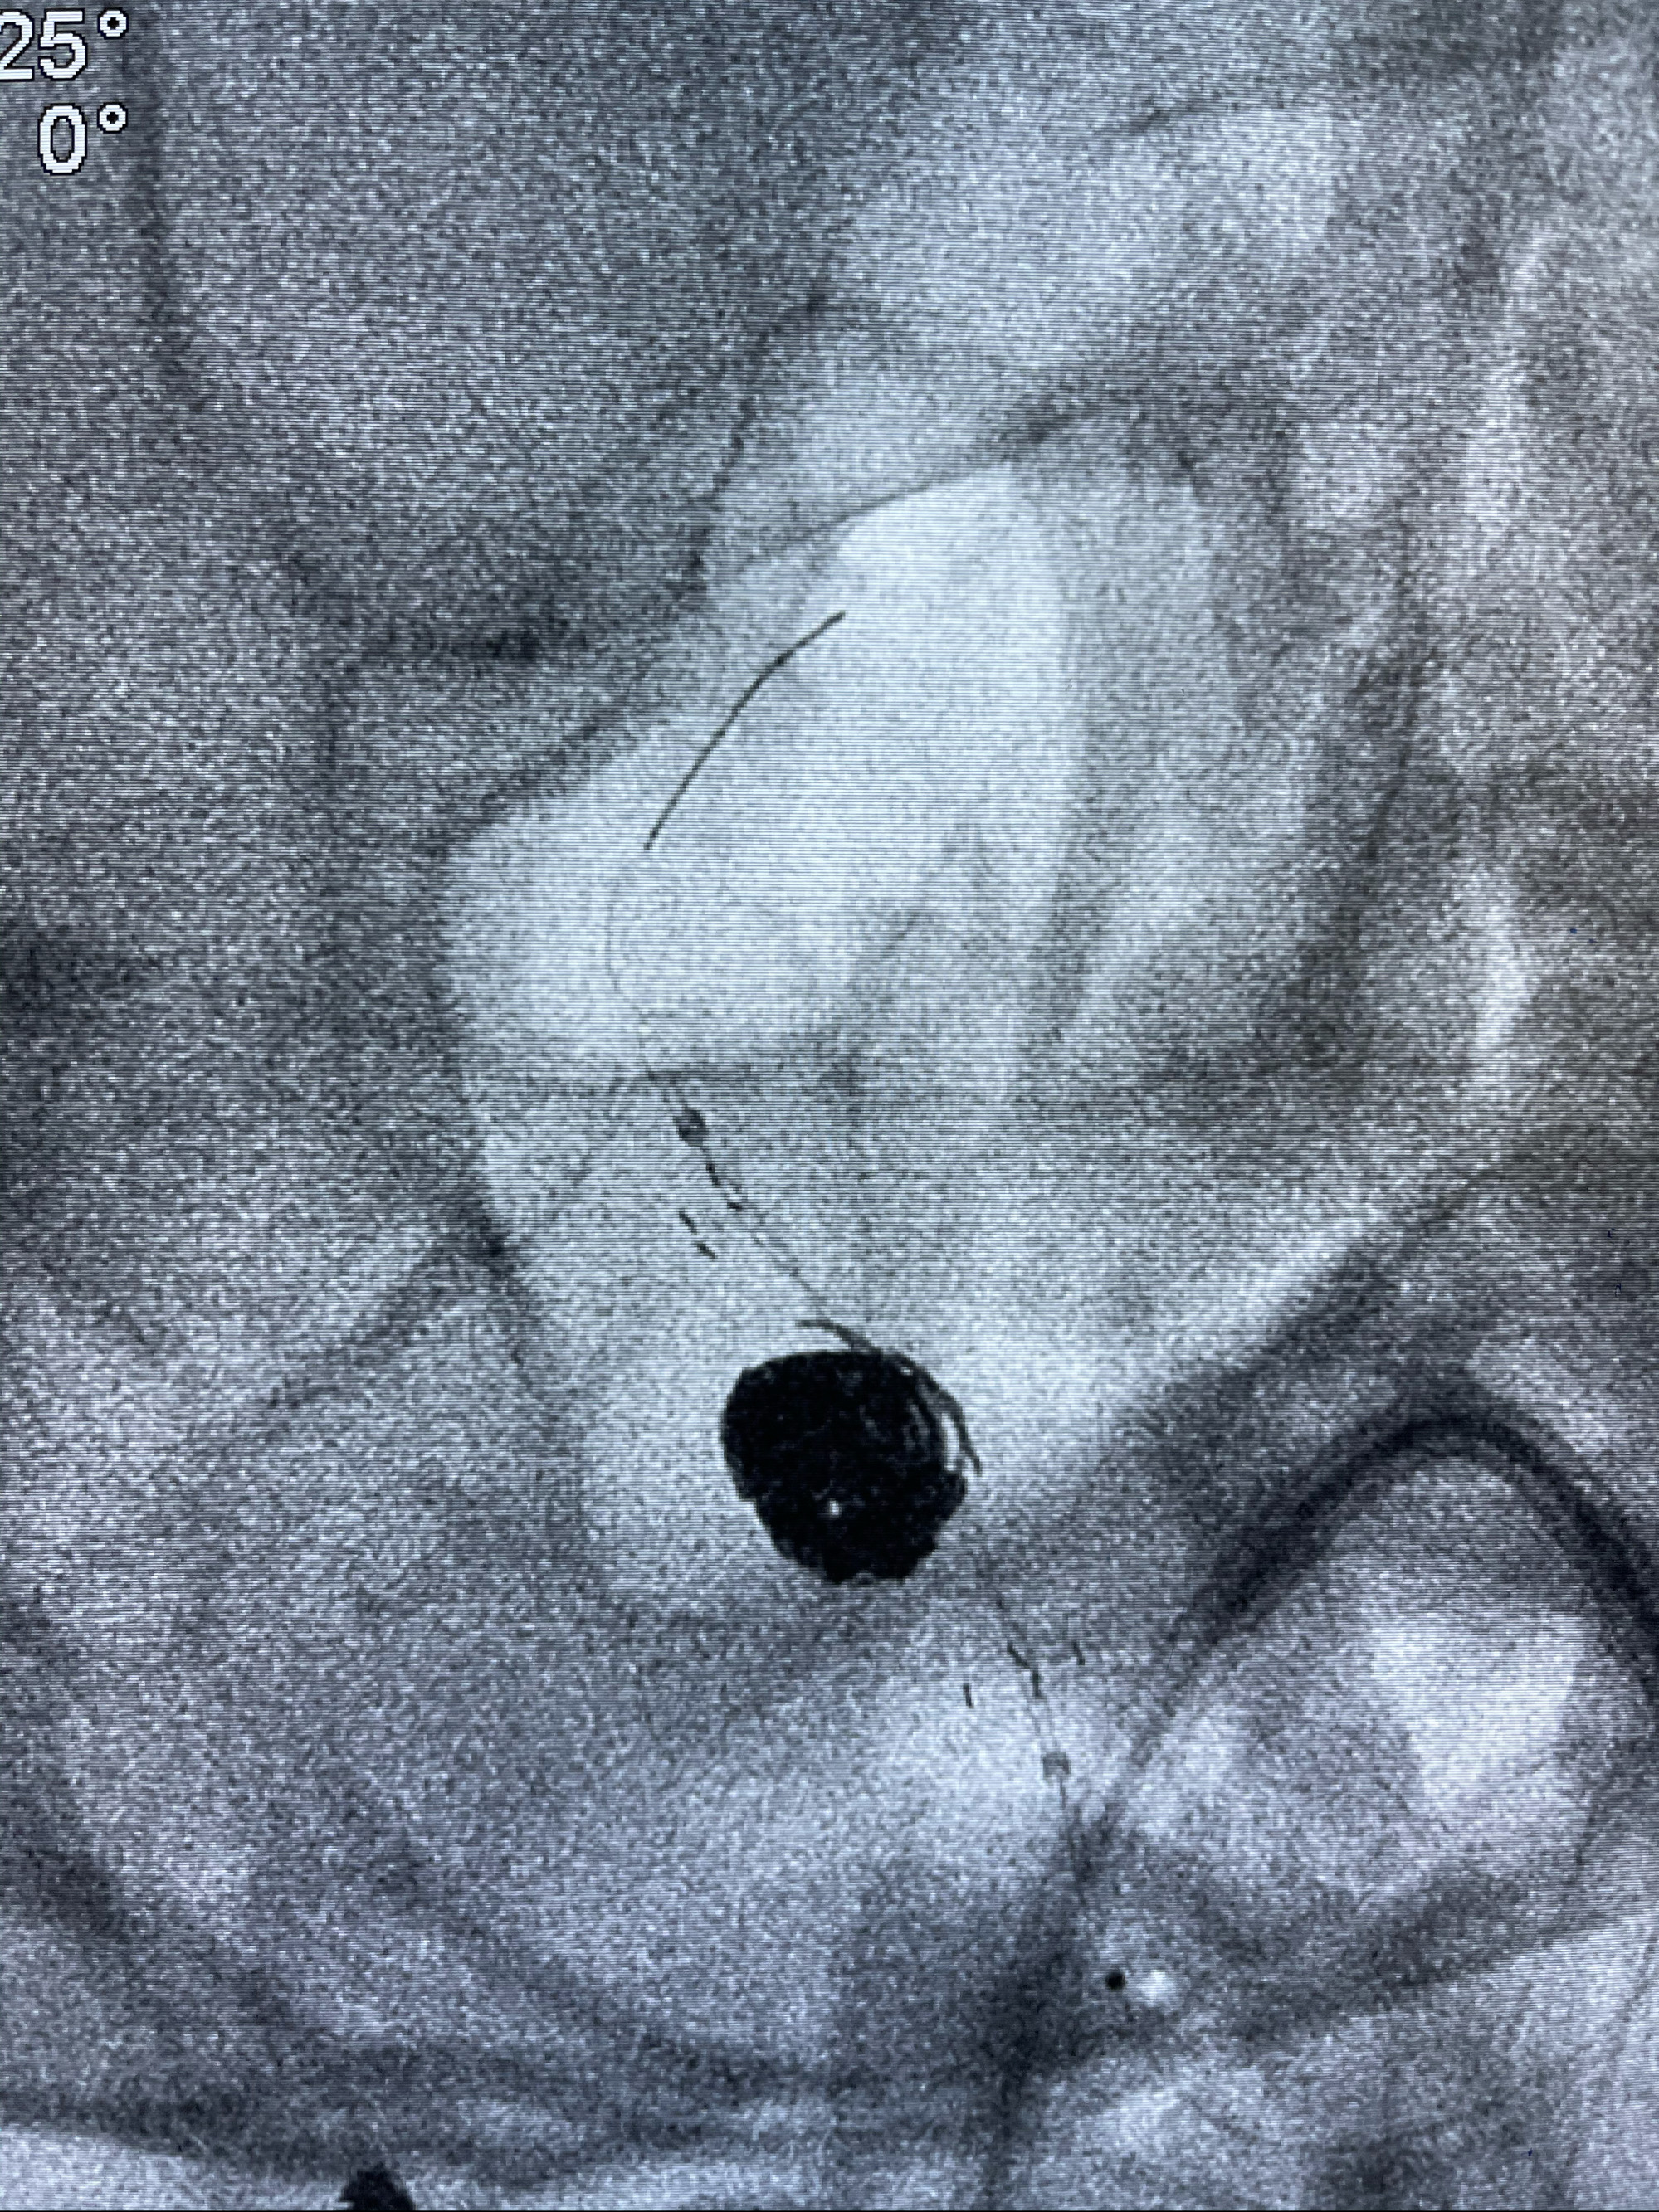

支架到位

支架释放,透视下